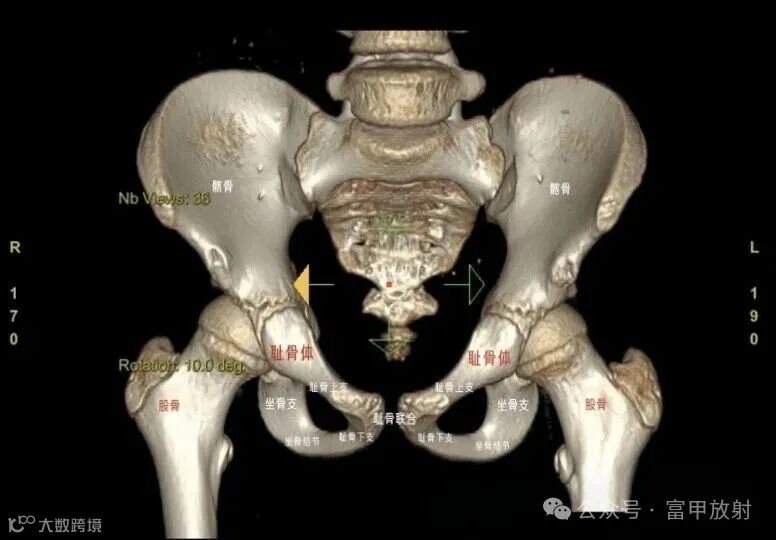

耻骨下支与坐骨分界在哪里?

坐骨结节是坐骨支的突起,是腘绳肌等附着的地方,耻骨结节是耻骨上支内侧缘的突起,腹股沟韧带附着点,在X线上坐骨结节也许估计到,耻骨结节基本上找不到,在这基础上作测量定位置,可靠性会不理想。以下这个简单的方法也许可以帮助到你。